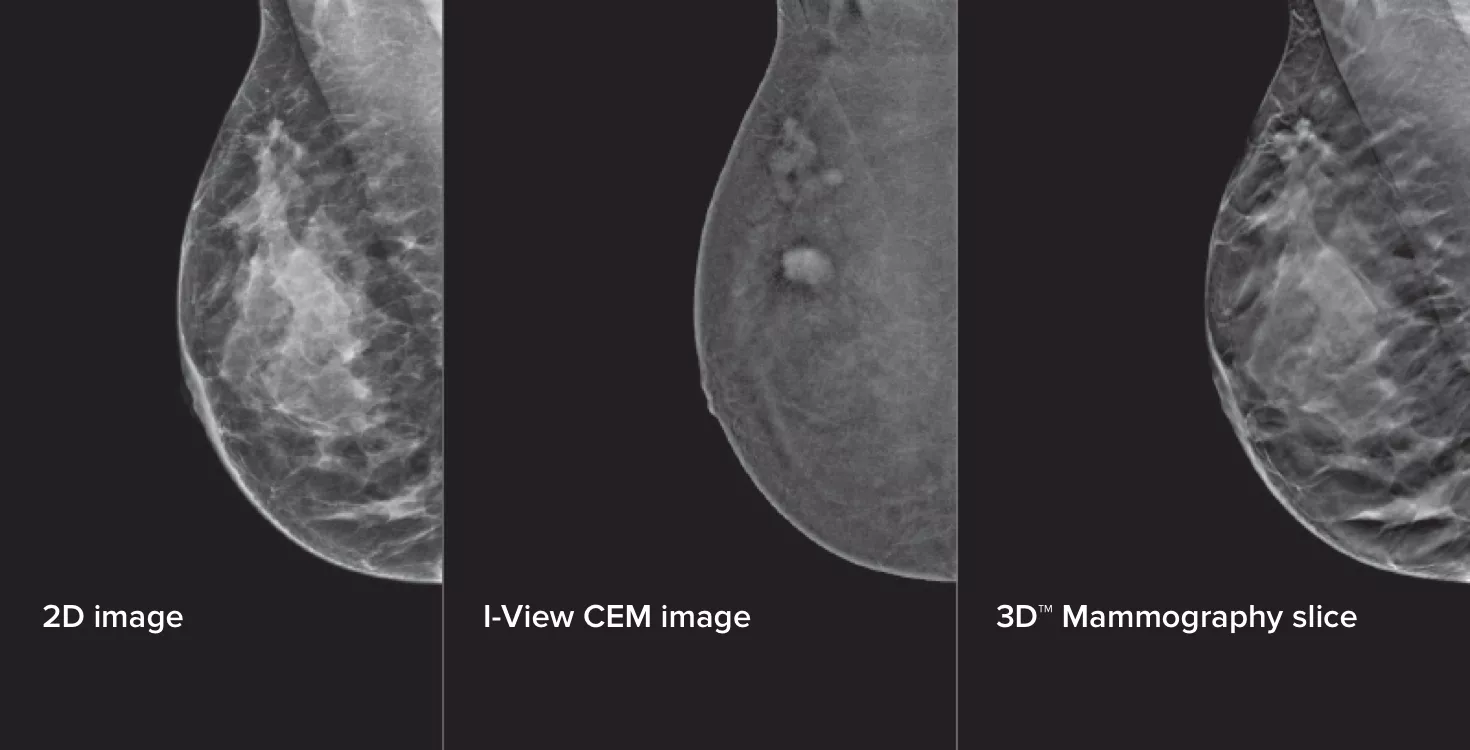

La mamografía con contraste (CEM), es decir, la adquisición de imágenes con medio de contraste yodado para poner de relieve las zonas de la mama con un mayor riego sanguíneo, puede ayudar a mejorar la visualización de las lesiones sospechosas. El software I-View permite combinar la potencia de la CEM con imágenes 2D y de tomosíntesis en una sola compresión para obtener imágenes anatómicas y funcionales en una única exploración.1

Este software captura información anatómica y funcional en una única exploración gracias a la posibilidad de adquirir imágenes 2D con contraste y de tomosíntesis en tan solo una compresión.1